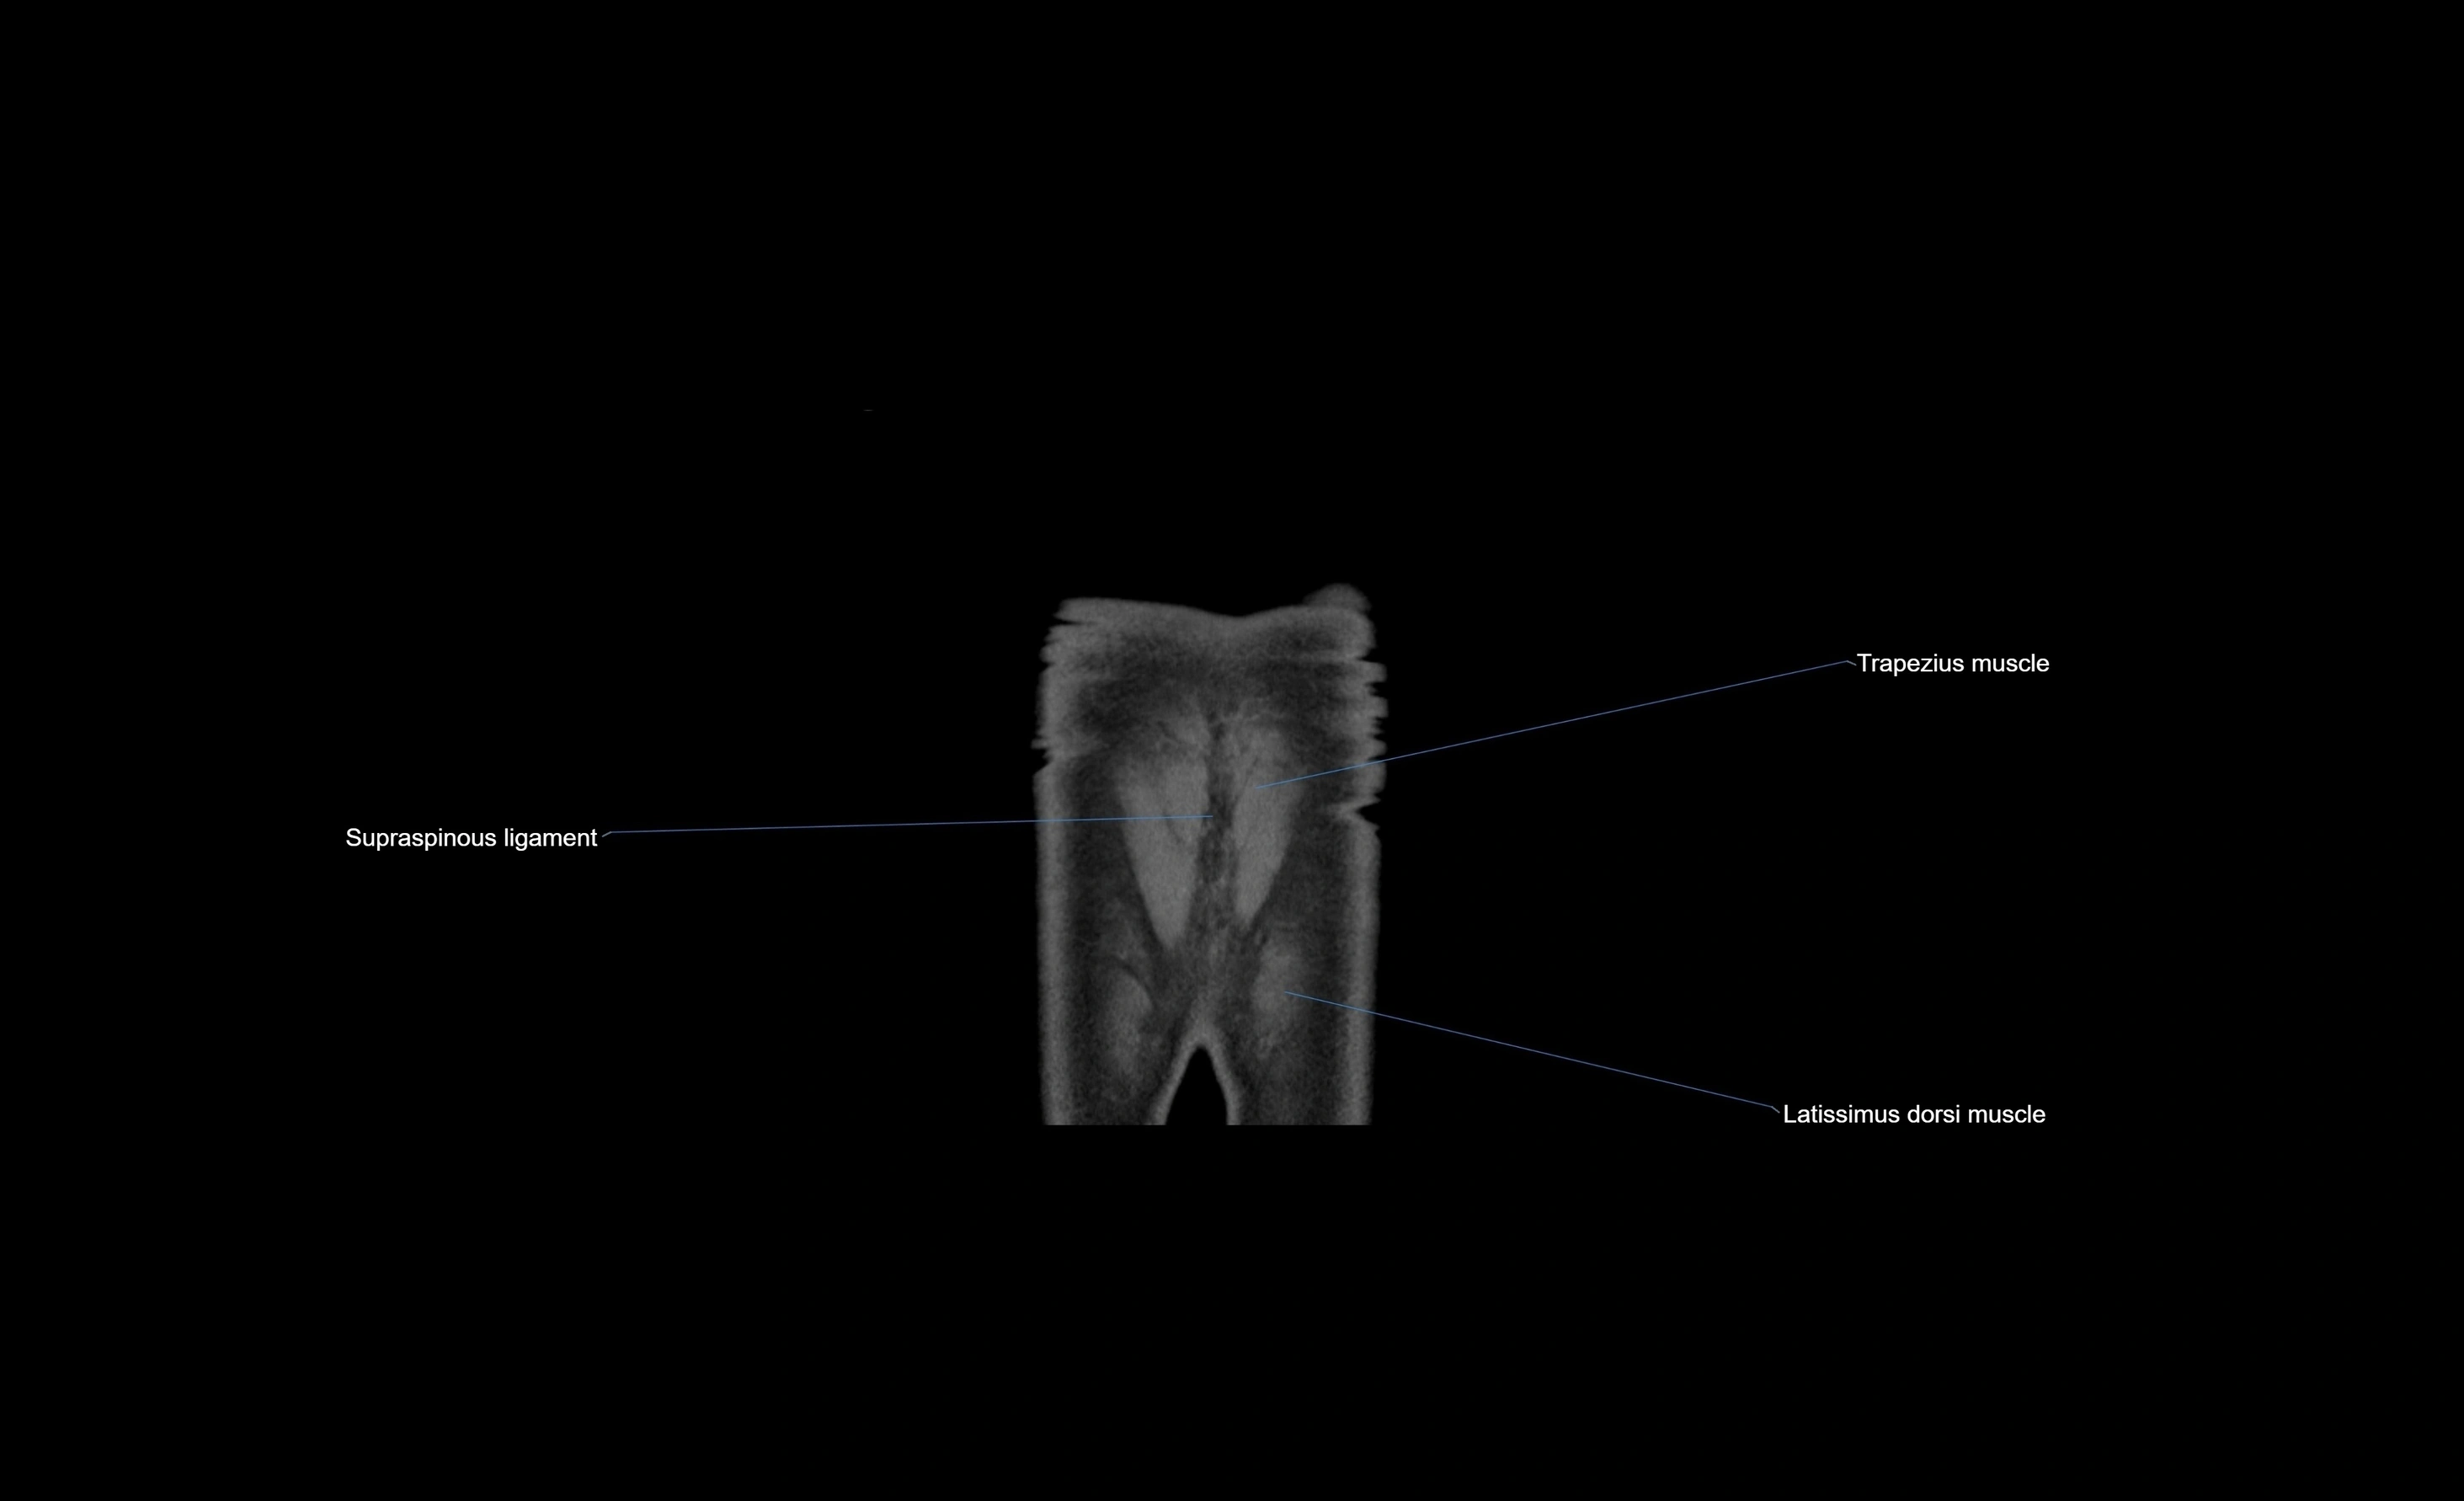

MRI images